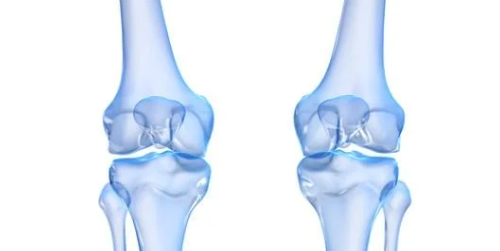

1. 강아지 슬개골 탈구란 무엇일까?

슬개골은 무릎뼈에 해당하는 부위로, 대퇴골과 경골 사이에서 관절이 정상적으로 움직이도록 돕는 역할을 합니다. 하지만 슬개골이 제자리에서 벗어나면 강아지슬개골 탈구가 발생하며,

- 무릎 관절의 불안정성

- 보행 장애

- 극심한 통증

을 유발하게 됩니다.